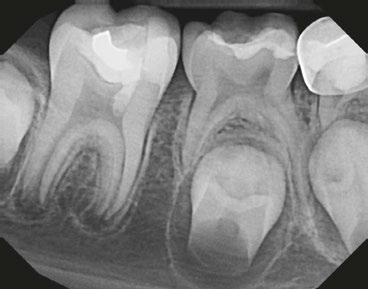

Several clinical solutions exist for primary anterior teeth with multisurface decay. Full coronal restoration of carious primary incisors may be indicated when caries is present on multiple surfaces, pulpal therapy is indicated, caries may be minor, but oral hygiene is very poor, or in a child with severe early childhood caries or a high caries risk diagnosis.1 Depending on the clinical scenario, a minimally invasive approach with the utilization of a high viscosity glass ionomer cement (HVGIC), with or without the combination of silver diamine fluoride (SDF) in a strip crown form, may pause the caries progression and provide an adequate clinical solution. Resin composite strip crowns have shown 80% retention rates and adequate parental satisfaction,1-4 although composite resin strip crowns have shown lower retention rates in teeth with decay involving three or more surfaces and particularly in children with a high caries risk4-6 (Figure 1). This could be from the continued high caries risk behaviors of the patient, as composite resin strip crowns in this population have shown to have increased inflamed marginal gingiva and gingival bleeding, increased plaque retention along the restoration, and loss of some restorative material.5,6

2: NuSmile® Anterior Zirconia crowns at 2-year follow up. Note the high amount of plaque accumulations along the untreated cuspid and existing stainless-steel crowns

A 2-year-old male who received full mouth dental rehabilitation (FMDR) under general anesthesia presented for his 6-month recall at 2-year post FMDR. He had significant plaque accumulations with poor oral hygiene along his existing stainless-steel crowns (SSCs) and non-treated teeth. Additionally, the patient had gingival bleeding and gingival inflammation

Figure 1: Occlusal films at recall visit in high caries risk patients showing loss of material and recurrent decay in composite resin strip crowns Figure

around these clinical sites. His anterior zirconia crowns showed healthy gingival margins with little-to-no plaque accumulations. This positive clinical finding is from the highly polished nature and biocompatibility of pediatric zirconia crowns. These restoration features limit plaque accumulations on the restoration and along the marginal gingiva, providing a localized positive aspect directly related to the choice of restorative material (Figure 2).

Case 2

A 3-year-old female presented with pulpal necrosis and abscess on #E and pulpal necrosis on #F. Extraction therapy or pulpectomy was offered. The family was highly motivated to retain #E and #F. The pulpectomy was performed with 0.02 K-Flex hand files, 3% NaOCl with a lateral vented needle, obturated with Vitapex (Neo Dental International Inc., Federal Way, Washington), a premixed paste of calcium hydroxide and iodoform. The access was filled with a HVGIC sealing the pulp therapy and increasing the clinical success by minimizing the potential for bacterial contamination. NuSmile ZR anterior crowns were selected as offering a full-coverage, esthetic, cemented restoration with no polymerization shrinkage when compared to a composite restoration. Crowns were cemented with NuSmile® BioCem (NuSmile, Houston, Texas). This is clinically beneficial as the provider would want to cement a restoration that provides limited microleakage minimizing the potential for bacterial contamination.15-17 At 6-month follow up, lesion healing had occurred with healthy gingival margins and no plaque accumulations (Figure 3).

A 4-year-old female presented with existing Silver Modified Atraumatic Restorative Technique (SMART) style restorations on #D, #E, #F, #G, and caries on other teeth. These anterior lesions

had been previously treated using SDF and covered with a HVGIC in a strip crown form. Though her lesions were stable from the clinical success of the SDF and HVGIC, these restorations were starting to fracture and demonstrate loss of material. The family wanted a more esthetic treatment option that would have a longer survivability. Additionally due to her high caries risk nature, a full coverage restoration with NuSmile® ZR anterior crowns were a more ideal solution in stabilizing her extensive decay pattern and covering staining from SDF therapy (Figure 4).

Figure 3: NuSmile® ZR Crowns were selected as a cementable full coverage restoration. At 6-month recall, apical tissues were healed with excellent gingival health Figure 4: SMART style restorations that were definitively restored with NuSmile® ZR Crowns as an esthetic option to cover SDF staining